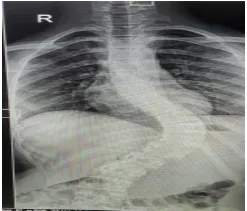

A 14-year-old female with 2 years of postmenarcheal presented with advanced scoliosis which was left untreated for 2 years. The deformity has Cobb's angle of 60°, which resulted in a non cosmetic deformity in the lower back (Image 1).This case certainly is within the usual range that indicates surgical intervention, with a curve which is clinically evident. The patient was advised to undergo surgery to prevent possible future negative impacts of the long-term signs and symptoms of scoliosis on her health. Considering this risk, the patient agreed to undergo surgery.

Pre OP x-ray

scoliosis-deformity-correction